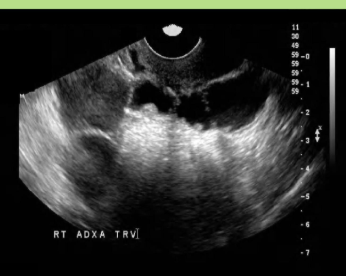

Stage 3 PID: Acute tubo-ovarian abscess

Multilocular retro-uterine/adnexal masses with debris

May see comet tail artifact due to air produced with bacterial infection

Septations

Irregular thick walls

Commonly bilateral

May see echogenic debris in pelvis

Tubo-ovarian abscess

Bilateral

Associated with PID and IUDs

Tubo-ovarian abscess USA

Abnormally thickened endometrium

Hydrosalpinx/pyosalpinx

Complex adnexal mass

Adnexal borders

Septations and debris

Gassy (DIRTY) SHADOWING may be seen